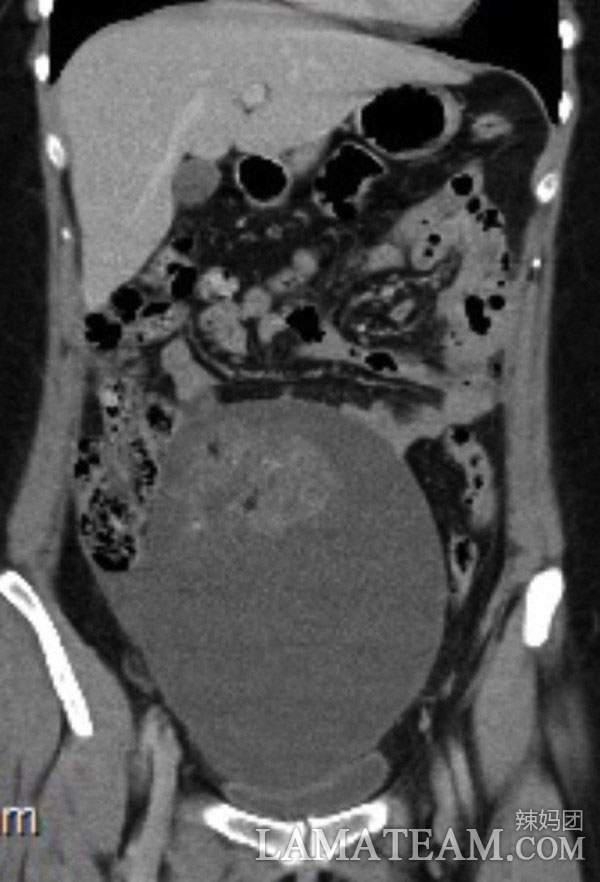

從片子中可以清楚地看到這個腫瘤已經佔據了她的整個胃部,還在壓迫著其他器官。這種情況只能手術,醫生先把腫瘤壓縮,到了可以移除的大小進行切除,然後修復卵巢和輸卵管,就這樣進行了4個小時的手術一切順利,而且還不會影響路易斯以後的生育。